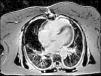

Considering the patient's ischemic burden, new-onset biventricular systolic dysfunction, and the absence of signs of pulmonary embolism, and as she was clinically stable after three days, it was decided to perform cardiac magnetic resonance imaging (MRI), which showed slight left ventricular systolic dysfunction, right ventricular dilatation with severe systolic dysfunction and transmural late enhancement in the mid-apical segments of the right ventricle, highly suggestive of RVI (Figures 3 and 4). Pulmonary artery angiography showed no signs of pulmonary thromboembolism. In this non-linear clinical case cardiac MRI was sufficiently informative to enable a diagnosis to be made: RVI.

The patient's clinical deterioration with acute decompensated heart failure in spite of therapy, including revascularization, fluid resuscitation and inotropic support, was a warning that further investigation was required. Cardiac MRI provided a more conclusive study of ventricular function and wall motion abnormalities, and gadolinium late enhancement demonstrated that the ischemic region was in the right apical ventricular wall. Cardiac MRI is the most sensitive method to assess right ventricular function. Right ventricular involvement usually occurs in the inferior segments and the apex of the right ventricle, regions in which imaging of wall motion abnormalities with echocardiography is particularly challenging.8 Most reports do not specify an optimal timing for MRI in an acute setting, and each situation calls for different timings.